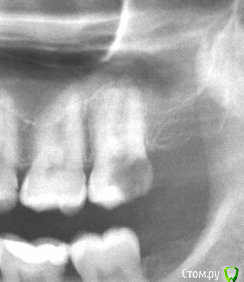

Xealer Опубликовано 4 декабря, 2018 Автор Поделиться Опубликовано 4 декабря, 2018 (изменено) Всем привет! Сделал новый снимок зубов в августе(справа просто вырезал кусок с первого снимка).С зубом 27 ничего не делал всё это время.Подскажите пожалуйста, нужно ли что-то делать с ним теперь? Можно ли просто оставить как есть?Или может можно вернуться к первоначальному плану - запломбировать каналы и надеятся, что инфекция ещё не успела проникнуть под корень? Можно ли по снимку определить, если проблемы под корнем зуба(периодондит и прочее)?Зуб особо не беспокоит и пульпа уже не реагирует. Изменено 4 декабря, 2018 пользователем Xealer Ссылка на комментарий